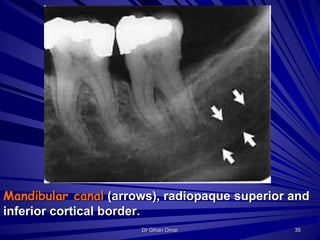

Mandibular canal (arrows), radiopaque superior and

inferior cortical border.

35Dr Gihan Omar

Mandibular canal (arrows),radiopaque superior and inferior cortical border. 35Dr Gihan Omar